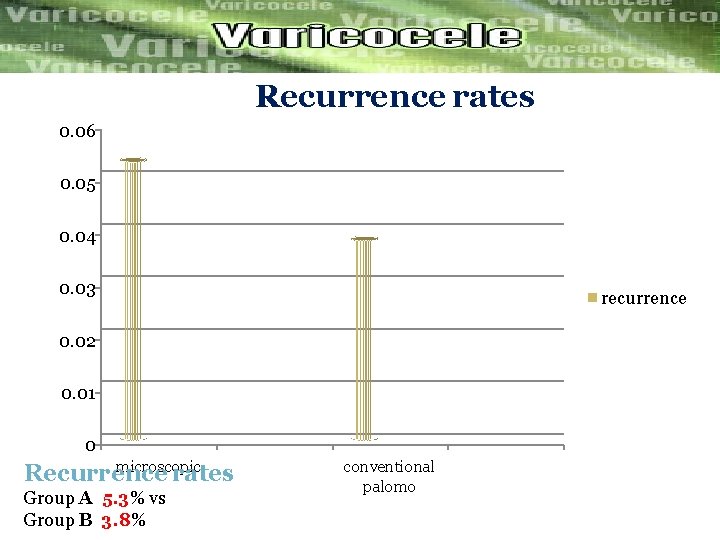

Objective: to evaluate the post operative complications Of microscopic and conventional palomo varicocelectomy Microscopic palomo varicocelectomy Group A(n=130) Conventional palomo Group B (N=130) The Postoperative complications and recurrence were compered Between the tow groups. The result after 1 year of follow up were…………. .

Recurrence rates 0. 06 0. 05 0. 04 0. 03 recurrence 0. 02 0. 01 0 microscopic Recurrence rates Group A 5. 3% vs Group B 3. 8% conventional palomo